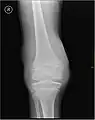

Radiographie montrant un début d'hémarthrose. Radiographie montrant un début d'hémarthrose.